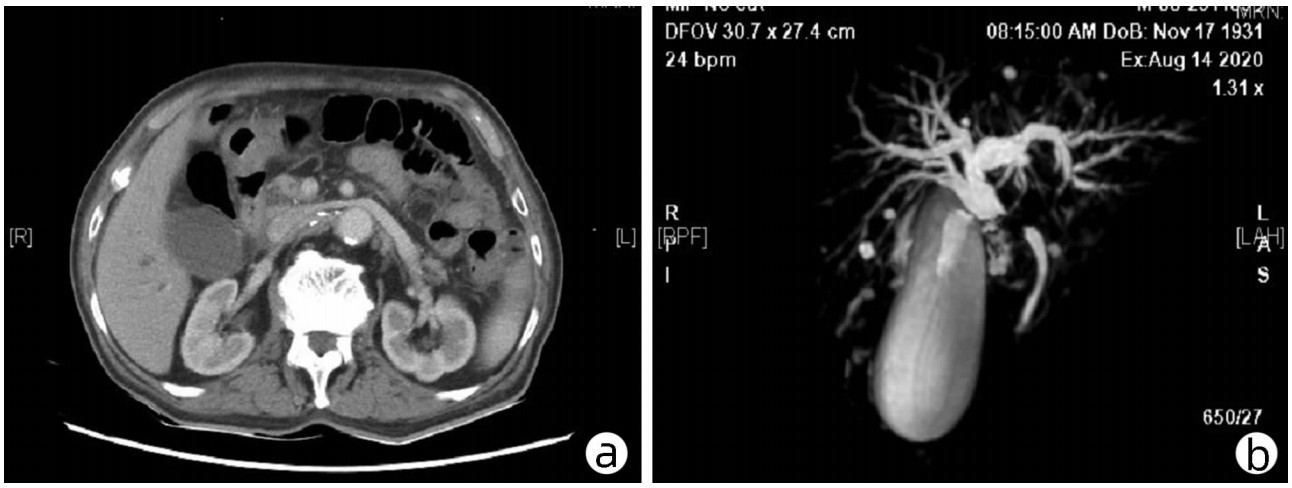

Hepatopulmonary syndrome after craniopharyngioma operation in children: A case report

Tingting DU, Hui YAO, Yakun LI, Xiaoli HUANG, Jie LUO

2022, 38(7): 1620-1625. DOI: 10.3969/j.issn.1001-5256.2022.07.030

Abstract(1022) HTML (325) PDF (2776KB)(75)

Abstract: